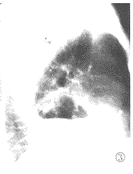

图2,3 左心尖外缘示有含气液囊腔。